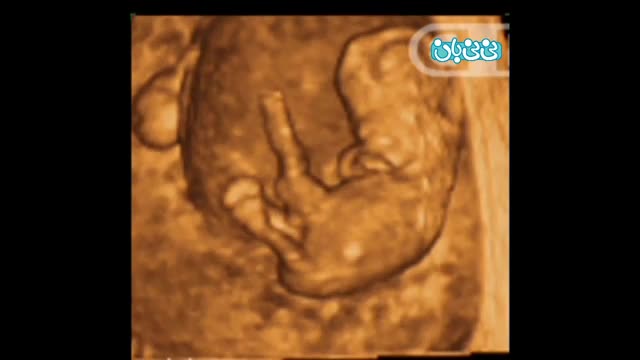

سونوگرافی چهار بعدی در بارداری هفته هشتم